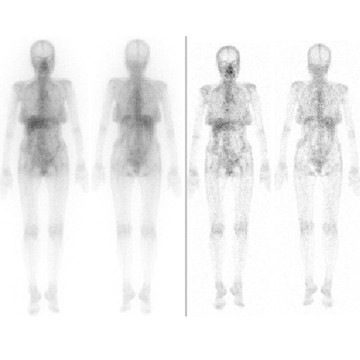

RI画像

ガリウムシンチ